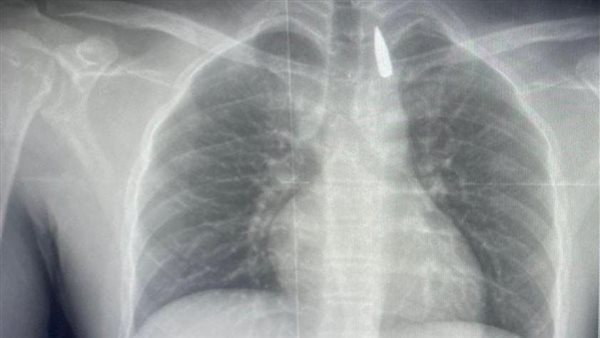

وأوضح الدكتور تامر عبد الله، عميد كلية الطب ورئيس مجلس إدارة المستشفيات الجامعية، أنه في يوم 21 أكتوبر 2025 تمكن فريق من أطباء قسم جراحة القلب والصدر والتخدير والمعاونين من إجراء جراحة دقيقة بالغة الخطورة لأحد المرضى المحجوزين من قطاع غزة، والذي كان قد تعرض لإصابة بطلق ناري في الرأس منذ فترة، استقر المقذوف على إثرها داخل تجويف القفص الصدري قرب الشريان الأورطي، وهو أكبر وأهم شرايين الجسم والمسؤول عن تغذية جميع الأعضاء الحيوية، وأضاف أن الفريق الطبي، رغم دقة الحالة وتعقيدها، نجح في استخراج المقذوف بأمان بعد عملية جراحية نادرة استمرت عدة ساعات داخل المستشفى الجامعي الجديد، حيث خضع المريض بعدها للرعاية الطبية اللازمة، وحالته حاليًا مستقرة وتحت المتابعة الدقيقة من الفريق المختص.